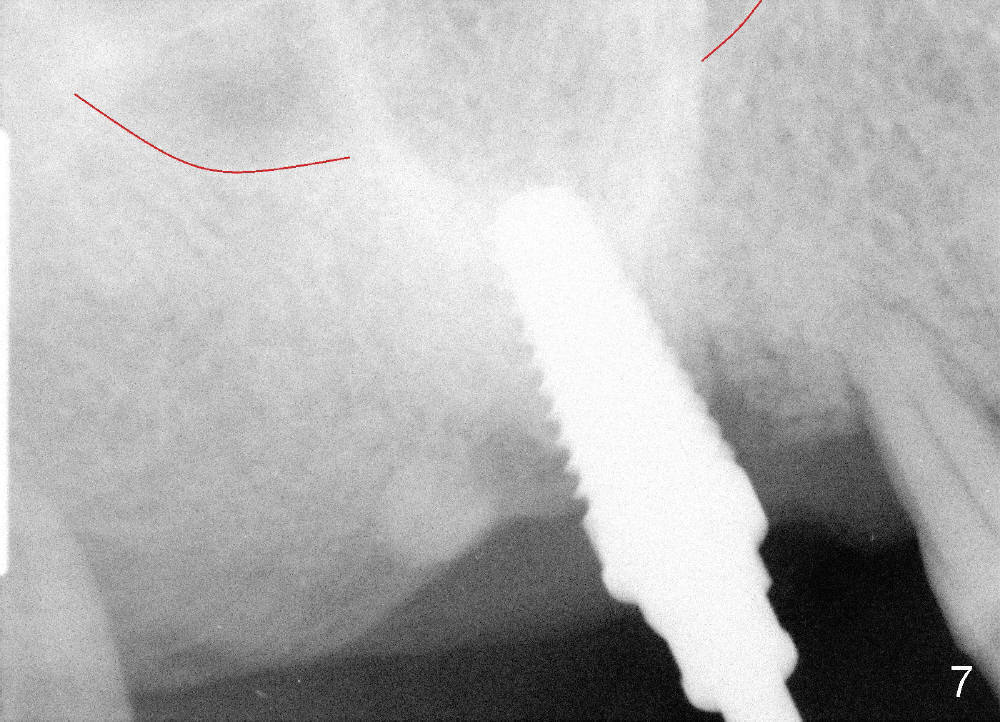

Osteotomy can be done in the palatal socket or the septum in this case to avoid implant thread exposure. Initial osteotomy is created in the palatal socket by using series of tap drills (4.5,5,6,7x17 mm) without stability or enough length (Fig.5; red line: sinus floor). The second osteotomy is made in the septum by using series of tapered osteotomes (2,3,4x17 mm), followed by 4.5x20 mm tap at depth of 17 mm with satisfactory binding (Fig.6). To avoid further sinus penetration and close the socket as much as possible, 5 and 6x17 mm taps are used at 14 mm deep (Fig.7). Nasal blowing reveals air leaking after the last tap. A 6x14 mm tapered implant is placed with insertion torque >60 Ncm (Fig.8). No bone graft is placed. The implant is surrounded by gingiva proximally and lingually and coagulation buccally. The wound is covered by perio dressing.